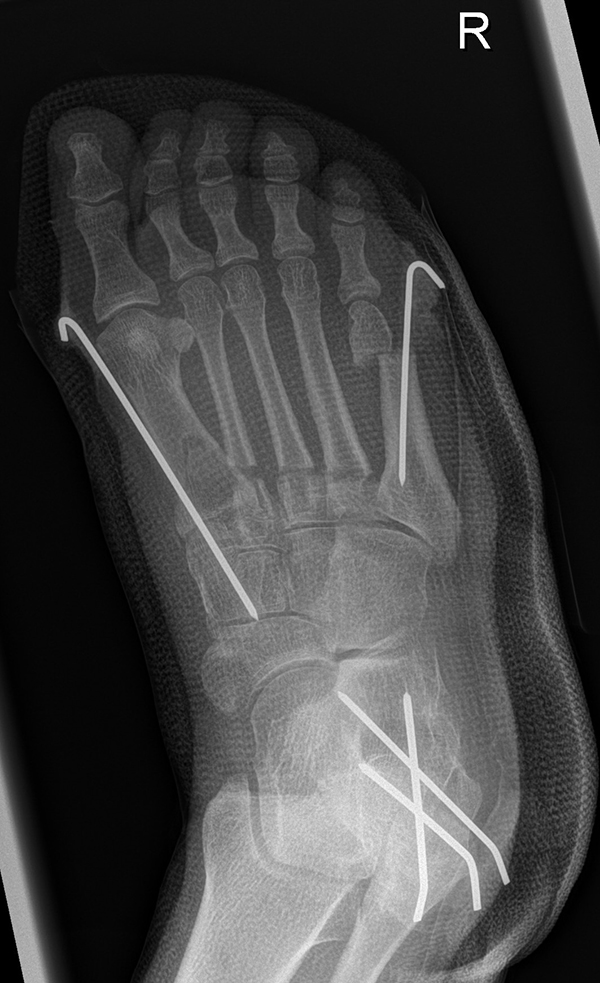

Zusätzlich schränken Wachstumsfugen die Wahl der Osteosynthese ein. Eine die Fuge kreuzende Osteosynthese ist ausschließlich mit Kirschner-Drähten möglich (Abb. 3).

Abb. 3 a-j: Beispiel einer Calcaneusverschiebeosteotomie mit offenen Wachstumsfugen und der entsprechenden Osteosynthese mit Kirschner Drähten. Lokalisation der Osteotomie (a), Lage der Fräse (b-d), Drahtlage mehrere Ansichten (e-h), Heilung der Osteotomie 4 Wochen postoperativ und Entfernung der Drähte (i-j).